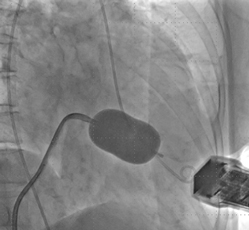

発作性心房細動の治療法の一つとして、冷凍アブレーションカテーテルがあります。バルーンに冷却剤を供給して、組織を凍結し、発作性心房細動を起こす原因の不要な電気回路を遮断します。

バルーンカテーテルは、発作性心房細動治療に安全かつ有効な医療機器で、世界700以上の施設で9万人以上の患者さんに使用されてきました。安全である理由は、合併症を起こす危険性が低いためです。またバルーン形状により、肺静脈への迅速かつ効率的なアプローチと治療(肺静脈隔離)を可能としました。従来の高周波アブレーションでは、スポット状の小さな絶縁部を何度も繋ぎ合わせて、肺静脈隔離を目指します。一方、バルーンカテーテルを用いた冷凍アブレーションでは、バルーンで肺静脈を閉塞して数回冷却するだけで、肺静脈の周りに連続的な絶縁部を一括で作製できます。